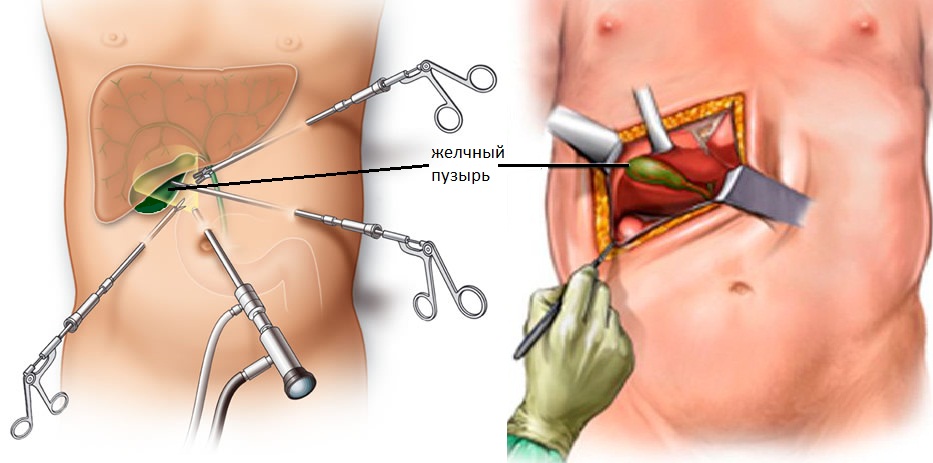

Анатомия и особенности Гартманова кармана желчного пузыря